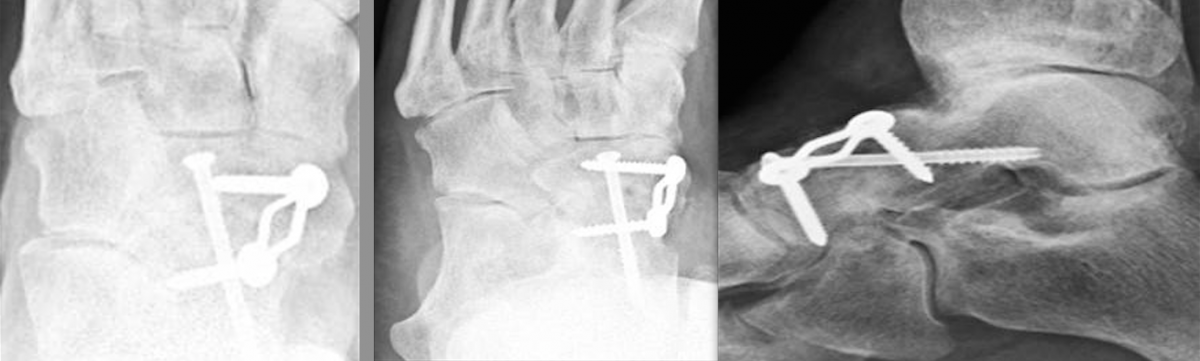

Locking Plates: What Have We Learned? Although traditional plate designs date back decades, these authors discuss the emergence and potential of locking compression plates, polyaxial locking plates, and minimally invasive plate osteosynthesis. HYPERLINK "https://s3.amazonaws.com/HMP/hmp_ln/imported/pt0915locking1ab.png" \t "_blank" The popularization of traditional plate and screw constructs dates back to the late 19th century as well as the efforts of the Belgian surgeon Robert Danis, MD.1,2 This discovery along with Danis’ publication of Over the past several decades, as surgeons have gained a better understanding of the utility of plate and screw constructs, the application of the devices has evolved. In addition to incorporating these devices into the surgical repair of fractures, surgeons may utilize them for joint arthrodesis and other reconstructive osseous surgeries. One advance with these modalities has been the advent and evolution of the locking plate construct, which has several applications within foot and ankle surgery. Reviewing The Different Kinds Of Plate Fixation HYPERLINK "https://s3.amazonaws.com/HMP/hmp_ln/imported/pt0915locking1cd.png" \t "_blank" Neutralization plates function as load-sharing apparatuses that shield lag screws from the torsional forces the surgeon encounters during range of motion.4 Buttress plates and anti-glide plates are load-bearing devices that can support a section or segment of bone, which are frequently areas of impaction associated with significant comminution of the cortex, thus leaving a compromised diaphyseal construct and/or voids within the cancellous bone. By fixing the plate proximally and distally to stable areas of bone, the surgeon can prevent the segments from re-approximating during axial loading.5 There are two kinds of compression plates: static compression plates and dynamic compression plates. With the static compression plate, the compression yielded at the fracture interface is secondary to the tension one applies to the implant. This technique is beneficial for those transverse or short oblique fractures when insertion of a lag screw is not attainable. In order to achieve compression, drill the initial screws eccentrically through oval holes in the plate away from the fracture site. As the screw heads contact the plate and sit centrally in the oval holes, the fragments compress together. The dynamic compression plate adheres to the tension band principle. This refers to the application of a plate on the tension (convex) side, preventing gapping that normally would occur and converting the distracting forces into compression forces. The placement of a plate to bone serves as both an expediter and a temporary inhibitor of osseous repair.5 HYPERLINK "https://s3.amazonaws.com/HMP/hmp_ln/imported/pt0915locking2abc.png" \t "_blank" Certain plate designs have addressed the effects of reduced blood flow that can occur underneath a plate due to reduced bone density. This plate-associated osteoporosis has a detrimental effect on the mechanical properties of healing bone. Limited contact dynamic compression plates were designed with recesses or undercuts in the plate to reduce contact between the plate and the bone, therefore reducing the risk of plate-associated osteoporosis. Recognizing The Potential Benefits Of Locking Compression Plates There have been efforts to improve the weakest part of the construct (the screw-bone interface) by increasing the contact area between the screw and the bone with the placement of screws in polymethyl methacrylate (PMMA) or by creating a single-beam construct. This is the principle behind locking plates with the creation of a construct to address the lack of motion between the components of the beam (i.e., the plate, screw and bone).6 HYPERLINK "https://s3.amazonaws.com/HMP/hmp_ln/imported/pt0915locking2def.png" \t "_blank" The locking compression plate arose from the desire to increase stability, which at the time was limited by the torque generated during screw purchase into the plate-bone interface. Cancellous, osteoporotic or pathologic bone and comminution limit the amount of torque that one can generate to enhance stability.7 This led to the development of the locking compression plate, which has the ability to preserve the blood supply to bone by reducing periosteal stripping. The traditional plating techniques provided stability by compressing the plate to the bone surface with the screws achieving bicortical purchase as the second point of fixation. However, locking compression plate technology features unicortical locking screws that can be an “internal fixator” that can act as a bridge over compromised bone.8 However, in areas or regions where high torsional and axial loads are expected, one should utilize bicortical locking screws. With locking plates, the sum of all the interfaces between the screws and bone equals the strength of fixation as opposed to the unlocked plates’ single screw pullout strength.7 One of the benefits of locking plates is their ability to be “bridge plates,” whereby they provide excellent axial and angular stability, preserve fragmentary blood supply, and reduce the risk of loss of reduction. Indeed, surgeons do not have to contour these plates anatomically to the bone, and the plates have the potential benefit of providing superior fixation in osteoporotic bone. Indications for the use of locking plates include diaphyseal/metaphyseal fractures in osteoporotic bone, multifragmentary diaphyseal/metaphyseal fractures, osteotomies in at-risk patients (poor bone stock, revisions, etc.), articular fractures, segmental fractures with multiple patterns, and any combination of the above.9 HYPERLINK "https://s3.amazonaws.com/HMP/hmp_ln/imported/pt0915locking3ab.png" \t "_blank" In their guidelines for using the locking compression plate, Gautier and Sommer emphasize the importance of the reduction technique, minimally invasive plate insertion and fixation to keep bone viability undisturbed.9 Pertinent Insights On Minimally Invasive Plate Osteosynthesis HYPERLINK "https://s3.amazonaws.com/HMP/hmp_ln/imported/pt0915locking3cd.png" \t "_blank" Minimally invasive plate osteosynthesis maintains bone vascularization with minimal periosteal stripping, thus improving bony consolidation and decreasing operative time, complications and infection rates. The application of a locking plate using the minimally invasive plate osteosynthesis technique generally consists of making small incisions proximal and/or distal to the fracture site, percutaneous reduction and subsequent extraperiosteal placement of the plate with any radiolucent percutaneous guide. Can Polyaxial Locking Plates Have An Impact? A recent study by Cullen and colleagues looked at a biomechanical comparison of polyaxial and uniaxial locking plate fixation in extra-articular proximal tibia metaphyseal fractures.10 A Closer Look At Potential Contraindications And Complications Currently, there are no absolute contraindications for locking plates. However, there are instances when applying them may be unnecessary. A good example would be in a case with a simple fracture pattern in a healthy patient with good quality bone. Another case would be a fracture pattern where the surgeon is trying to achieve compression through the plate itself without the addition of a lag screw. Also, if a patient has an oligotrophic non-union and the cause of the delayed healing is not related to an insufficient amount of stability, one should not employ locking plates. Another matter to keep in mind is the increased cost of a locking plate-screw construct versus traditional plate-screw designs, which in some cases can be substantial. As always, consider the possibility of a metal allergy or intolerance. HYPERLINK "https://s3.amazonaws.com/HMP/hmp_ln/imported/pt0915locking4def.png" \t "_blank" One of the more common complications with locking plates is creating an environment of too much stability, thus becoming “non-union generators.”11 Final Thoughts As we previously discussed, it is important to tailor the fixation of choice to the fracture pattern and location, the underlying bone quality and the overall needs of the patient. We still need to see more clinical data on locking plate technology in order to determine specific clinical scenarios in which the additional cost may be justified. Dr. Fidler is a Fellow at the Orthopedic Foot and Ankle Center in Westerville, Ohio. Dr. Prissel is a Fellow at the Orthopedic Foot and Ankle Center in Westerville, Ohio. Dr. Hyer is the Fellowship Director of the Advanced Foot & Ankle Surgical Fellowship in Westerville, Ohio. He is a Fellow and a member of the Board of Directors for the American College of Foot and Ankle Surgeons. References 1 2 3 4 5 6 7 8 9 10 11